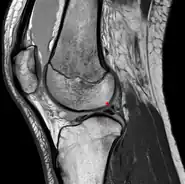

Posterior meniscofemoral ligament (Wrisberg) behind the posterior horn of the lateral meniscus close to its insertion. Sometimes wrongly interpreted as a meniscal tear.

The posterior meniscofemoral ligament (also known as the ligament of Wrisberg) is a small fibrous band of the knee joint. It attaches to the posterior area of the lateral meniscus and crosses superiorly and medially behind the posterior cruciate ligament to attach to the medial condyle of the femur.[1]

The posterior meniscofemoral ligament is found in 64.4% of the subjects in MRI scan of the knee.[1]